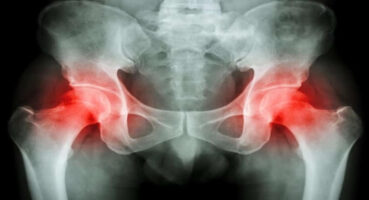

Hastalık farkındalığı ve önleme programları kemik erimesi hastalığında büyük önem taşıyor. Amgen, 50 yaşından sonra her 3 kadından 1'inde ve her 4 erkekten 1’inde görülen ve sağlığı tehdit eden hastalıklardan bir tanesi olan kemik erimesi tedavisi için bilimin ışığında ilerliyor. Kemik erimesine bağlı kırık konusunda, kadınların bilinçlenmesini ve sevdiklerini bilgilendirmelerini sağlamak amacıyla dikkatkirilabilir’u hayata geçiren Amgen, platformun Instagram ve Facebook hesapları aracılığı ile de toplumu bilinçlendirmeyi hedefliyor. Sitede hastalığın belirtilerinden tanısına, tedavi yöntemlerinden beslenme ve egzersiz önerilerine kadar geniş bir yelpazede içerik arşivi yer alıyor.